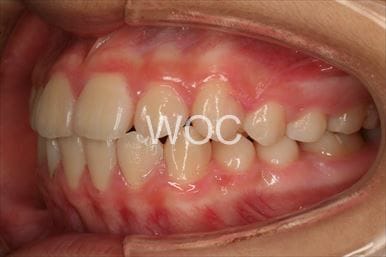

出っ歯エッジワイズ装置

特に装置の希望はなかったので、エッジワイズ装置を選択。

歯の移動量が大きいので歯根吸収の可能性がありましたが、目立った吸収は見られませんでした。-

- 年齢:17歳女性

- 主訴:出っ歯、前歯のガタガタが気になる

- 基本矯正料金:78万円

- 治療期間:1年2ヶ月

- 抜歯部位:上顎両側第一小臼歯